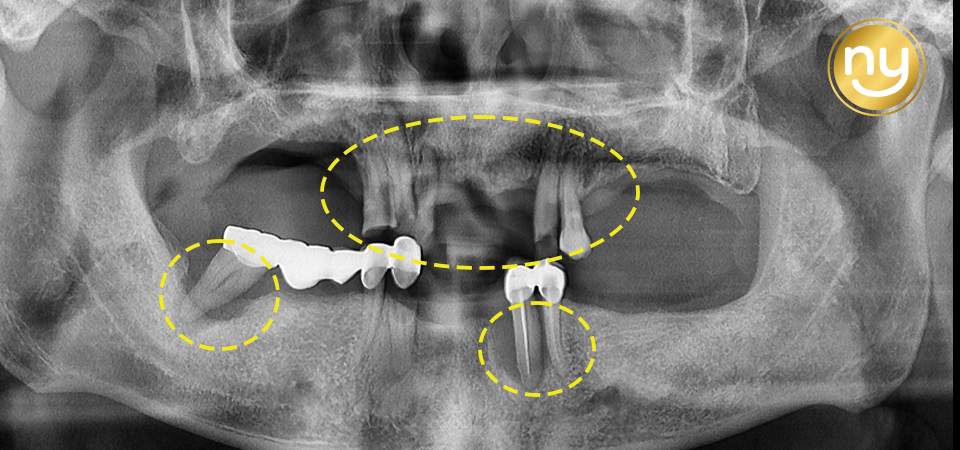

처음 본원에 내원하셔서 찍은 파노라마 사진입니다.

전체적으로 잇몸뼈의 소실이 심하고

하악의 브릿지와 크라운을 수복한 치아들도

염증이 발생되어 있는 것을 보실 수 있는데요.

염증과 치주 질환으로 인해 치아 흔들림이 심해 상악 송곳니 2개와

작은 어금니 1개를 제외하고는 살릴 수 있는 치아가 없어서

나머지 치아들은 발치를 진행하기로 했습니다.